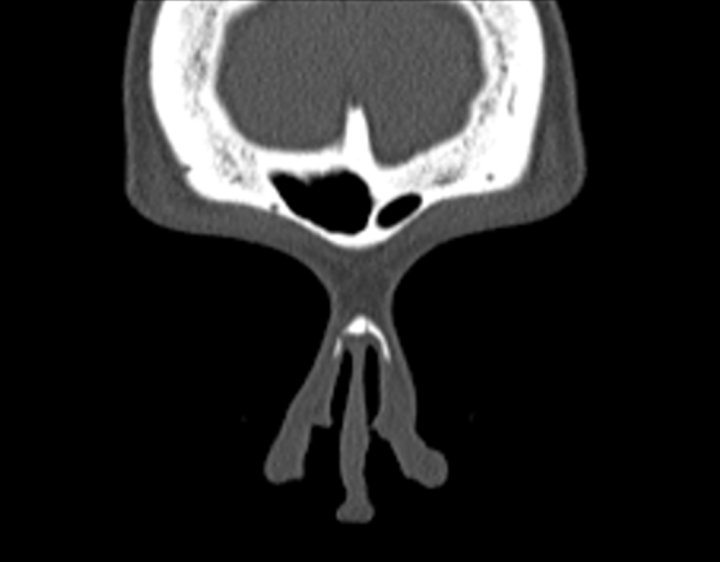

Click any image for labels.